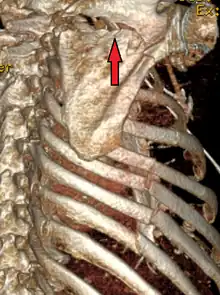

| A right sided scapula fracture with rib fractures underneath seen on a 3D reconstruction of a CT scan | |